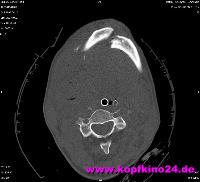

Der Ast, der durch die Frontscheibe ins Auto gepeitscht kam, hat mir den

ersten Halswirbel (Atlas) und zweiten Halswirbel (Axis) gebrochen.

Der runde Punkt auf dem Röntgenbild im oberen Teil des Atlas ist der

Dens des Axis - der Zahnfortsatz

- der in den Atlas hineinragt und die Nein-Bewegung des Kopfes erlaubt.

Der 1. Halswirbel (Atlas)

Der Pfeil zeigt auf die Abruchstelle, die sich nach innen bewegt hat und 3 mm vor dem Rückenmark (dunkler Fleck) lag. Auf der rechten Seite sieht man die gesunden Seite. Es haben 3 mm an einer Quetschung des Rückenmark "gefehlt". Eine Quetschung hätte eine Querschnittlähmung zur Folge gehabt.

Der Atlas ist an 2 Stellen mit dem Hinterhauptknochen mittels sog. Eigelenk verbunden. Das ermöglicht das Ja-Sagen sowie das seitliche Abkippen des Kopfes. Auch dort befand sich an der rechtes Seite des Atlas eine Fraktur. |